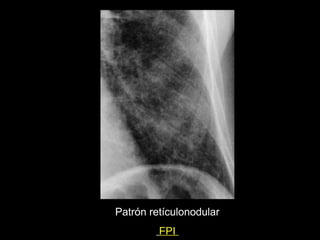

Patrón retículo nodular

Patrón retículonodular

FPI